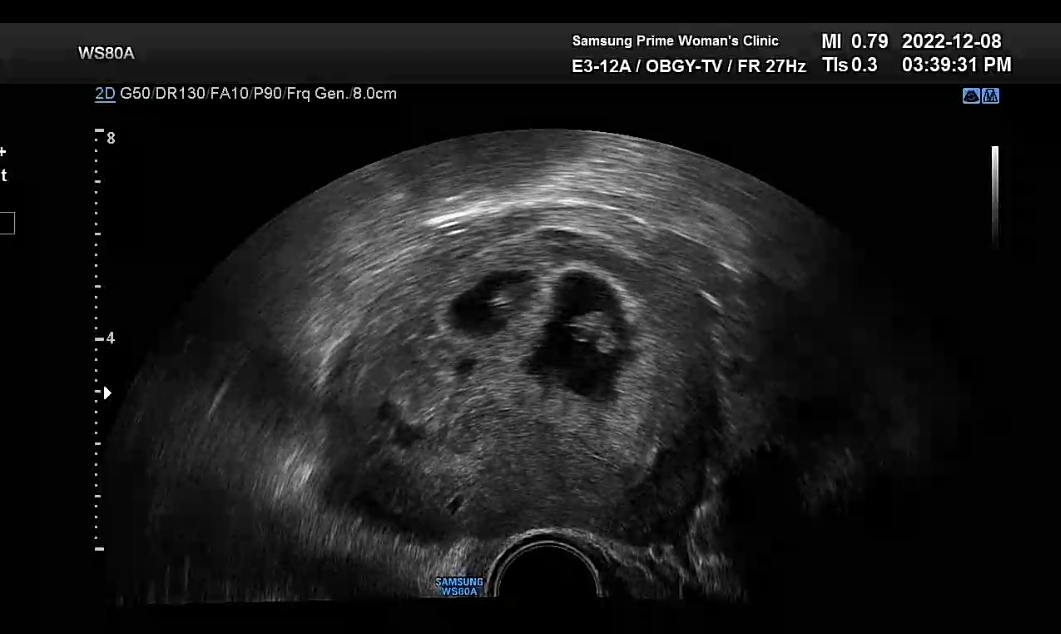

초음파 보니 아직은 아주 작은 우리 아가들의 심장이 콩닥콩닥 열심히 뛰는 모습이 보였다.

작은 우리 아가들 열심히 잘 자라주고 있구나 하는 생각에 우리 아가들이 기특하기까지 했다.